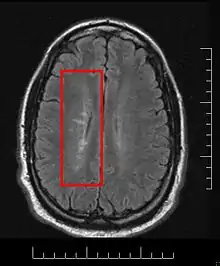

MS lesions

Normally MS lesions are small ovoid lesions, less than 2 cm. long, oriented perpendicular to the long axis of the brain's ventricles [18] Often they are disposed surrounding a vein[19]

Active and pre-active lesions appear as hyperintense areas under T2-weighted MRI. Pre-active lesion here refers to lesions localized in the normal appearing white matter, without apparent loss of myelin but nevertheless showing a variable degree of oedema, small clusters of microglial cells with enhanced major histocompatibility complex class II antigen, CD45 and CD68 antigen expression and a variable number of perivascular lymphocytes around small blood vessels[20]